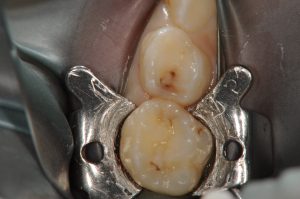

今回は、大学病院当時の症例として虫歯がある状況と虫歯を完全に除去した時の写真をあげようと思います。

削ってない方は、見ると、歯に黒い部分がありますが、そんなに大きくないようにも見えると思います。

しかし、削った後の写真を見て見ると、上の歯は、歯の1/2以上を削っている状態であり、神経までギリギリの状態となっております。

もちろん、この子も実際に、痛いなどという症状は一回も感じていないようです。